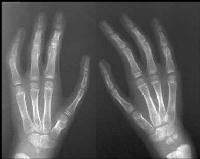

| Case 3. (case of unknown surgeon). The index fingers were probably narrow to begin with, and the current metacarpal length detract from the final result. |

![]() |